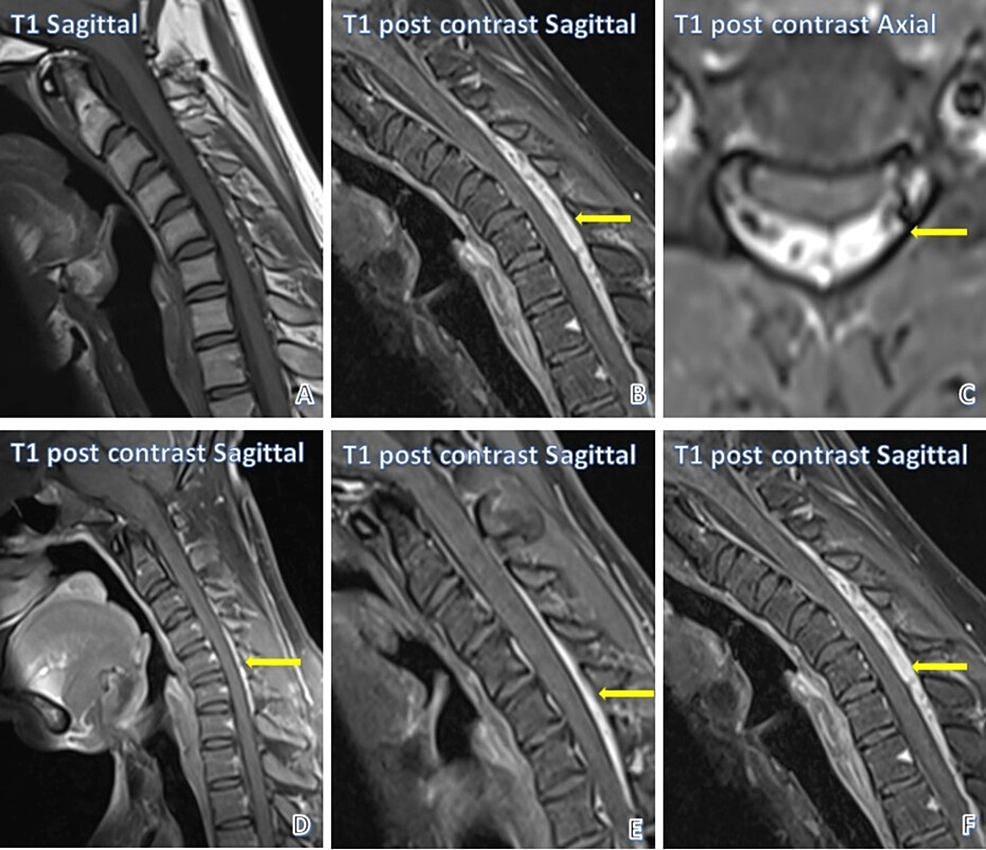

From www.cureus.com

Cervical Spine Resonance Imaging Findings in Hirayama Disease C Spine Mri Reddit Please refer on normal spine imaging examples article for more examples, including other. The cervical spine is the portion of your spine that runs through your neck. My neuro ordered a spine mri, but only cervical spine. A cervical spine mri scan is used to help diagnose:. This section of the website will explain how to plan for an mri. C Spine Mri Reddit.